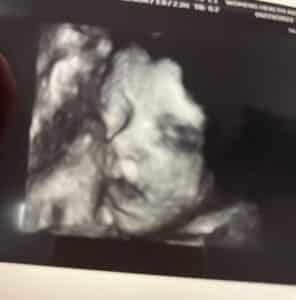

I found out I was pregnant in April 2022. I am currently 29 weeks with our fifth baby, our third girl.

I will have a repeat c-section in about 9 weeks. We are so excited to hold this sweet girl in our arms and love on her.